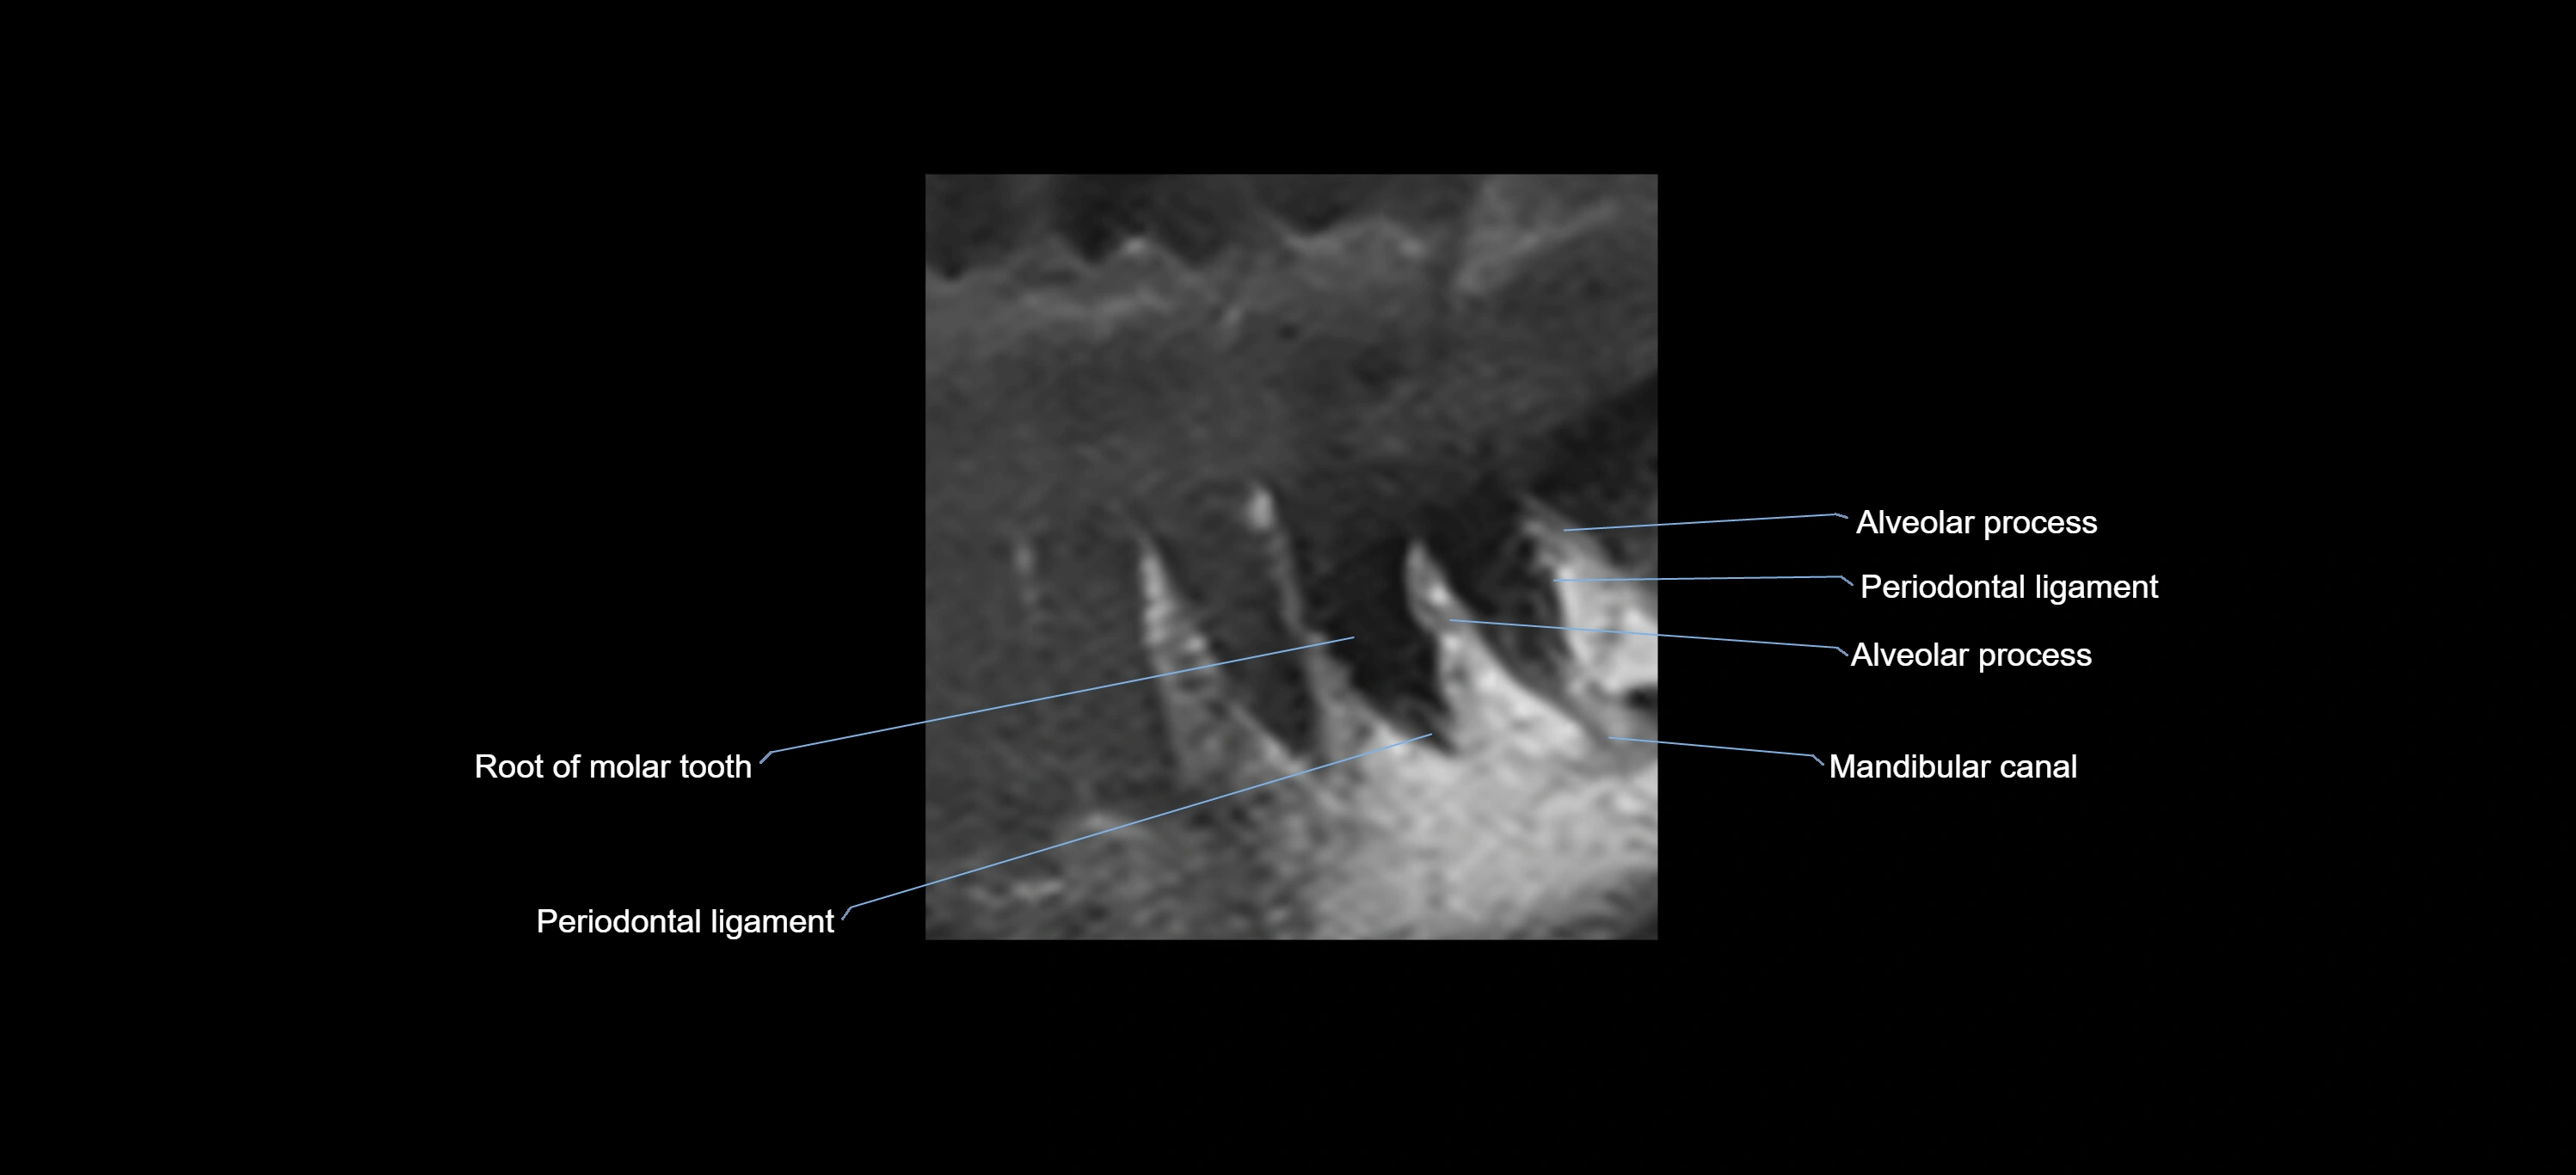

- Mandibular canal

- Periodontal ligament

- Root of lower molar tooth